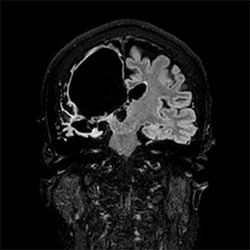

Brain